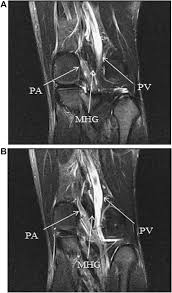

The patient was treated with myotomy of the medial head of the gastrocnemius muscle and concomitant endarterectomy of the popliteal artery. In these cases a bypass with either a vein or a synthetic graft is required to restore normal. Treatment In cases of anatomical PAES surgery is almost always the most effective treatment.

They later reported four more cases and claimed that the incidence of this pathology in patients younger than 30 years old with claudication was 40. Thrombolytic therapy can be used to treat acute and subacute occlusions of the popliteal artery due to underlying stenosis. Early diagnosis through a combined approach careful physical examination and history-taking duplex ultrasonography computerized tomography and angiography is necessary for exact diagnosis.

Thrombolytic therapy is most successful if initiated within 2 weeks after thrombosis 6. During this surgery an incision is made behind the knee to access the popliteal artery and the muscle tendon or band causing the compression is. Because the types of entrapment vary surgery can include fasciotomy removal of the offending bands of muscle muscle transfer fossa decompression or any combination of the above.